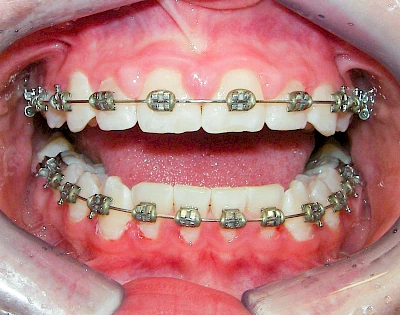

Sonderform: Schlupfwinkelinfektion

Im Laufe der menschlichen Entwicklung haben sich die Kiefer aufgrund unserer Nahrungsumstellung rückgebildet. Die Weisheitszähne haben daher oft keinen Platz mehr. Bei ca. 30 % der Menschen sind diese Zähne schon gar nicht mehr angelegt. Zum Teil liegen die Zähne versteckt (retiniert) im Kiefer und sind nicht sichtbar. Hin und wieder brechen die Zähne zwar durch die Schleimhaut, aber nicht vollständig – es handelt sich um einen erschwerten Zahndurchbruch (dentitio difficilis). Dann sind die Zähne noch teilweise bedeckt von einer "Schleimhautkapuze". Gehen hier Speisereste und Bakterien unter die Schleimhautkapuze kann sich eine sogenannte Schlupfwinkelinfektion bilden. Diese Entzündungen treten spontan auf, sind häufig sehr schmerzhaft und die Mundöffnung ist eingeschränkt. Hier ist umgehend der Zahnarzt zu kontaktieren.